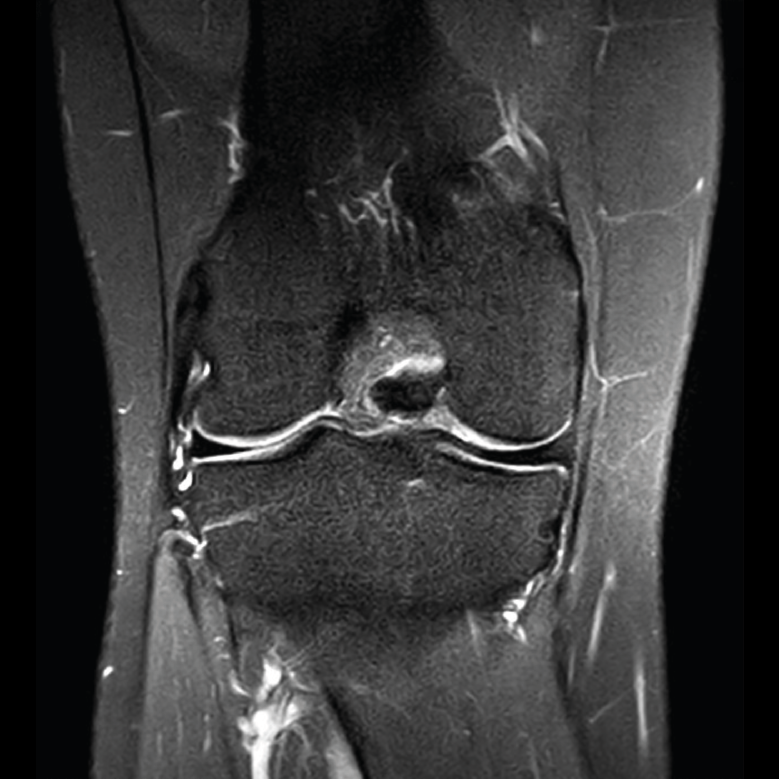

4. Lesiones isquémicas

4.1. Necrosis avascular (NAV)

En la NAV (aséptica, isquémica u osteonecrosis), hay una pérdida del flujo de sangre en el tejido óseo que hace que el hueso muera.

Se produce por un trastorno de la irrigación sanguínea o por lesiones celulares en el hueso y en la médula ósea.

Puede observarse en la RM la disminución de la intensidad de la lesión mucho antes de que se aprecie con otras pruebas diagnósticas (Figura 51).

Figura 51. Corte de secuencia T2 Fat-Sat coronal: lesión osteocondral con necrosis avascular del fragmento óseo.